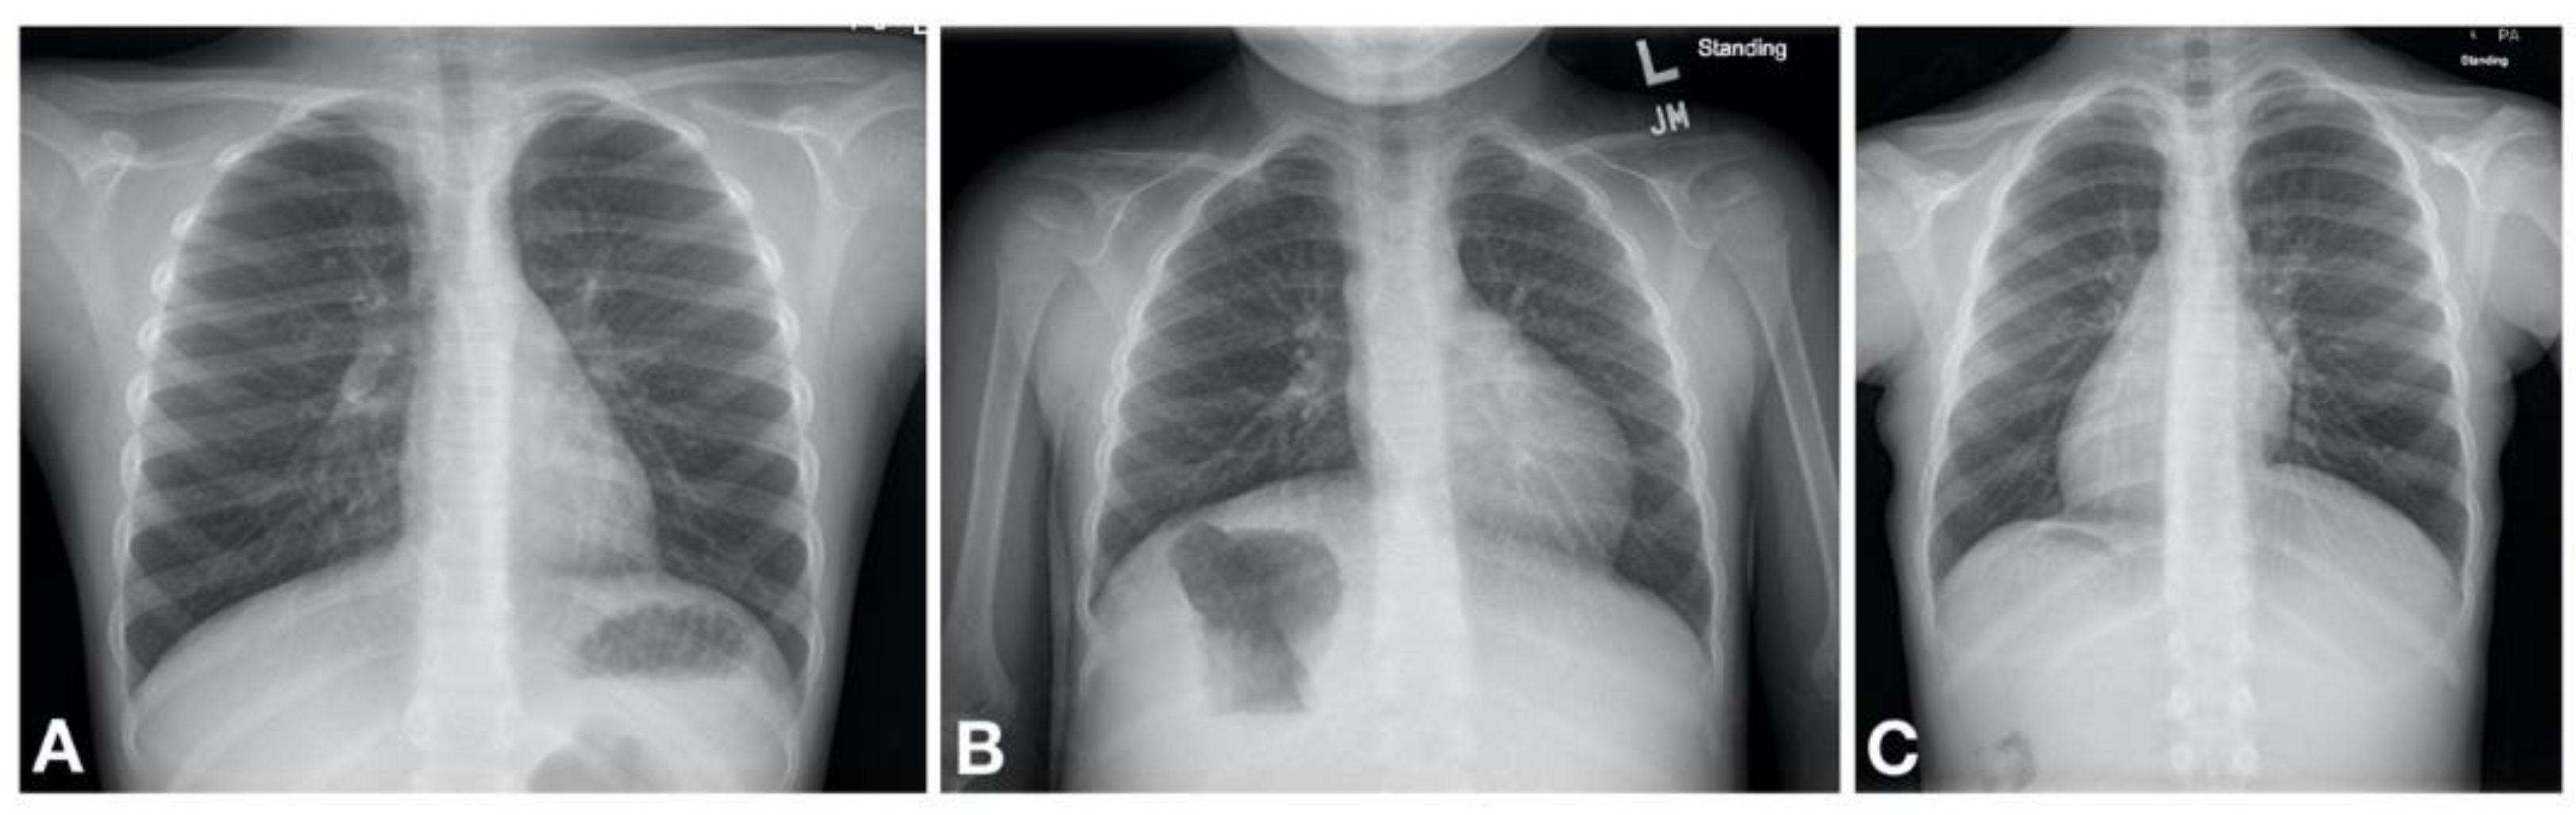

Figure 2. Machogu et al. Laterality defects found on chest radiography of patients with PCD. (A) Normal; Left sided cardiac apex with left sided stomach and right sided liver (B) Situs Ambiguous; Left sided cardiac apex with right sided stomach and left sided liver (C) Situs Inversus Totalis; right sided cardiac apex with right sided stomach and left sided liver.

The abnormal function of motile cilia results in impaired mucociliary clearance from the respiratory system and stagnation of purulent mucus that inevitably leads to recurrent and chronic oto-sino-pulmonary infections [18]. The PCD clinical phenotype is heterogenous and disease progression is likely related to the associated gene mutations [19]. Nonetheless, nearly all patients with PCD have early onset, year round wet and productive cough, while about 80% have early onset, year round daily nasal congestion and chronic sinusitis [20]. Recurrent bronchitis and pneumonia ultimately leads to development of bronchiectasis [21]. Additional clinical features include situs inversus totalis (SIT) in about half of the patients [18] while about 12% are reported to have other forms of heterotaxy [22] (Figure 2). Infertility is present in nearly all male patients due to reduced motility of spermatozoa [18]. Table 1 summarizes the clinical manifestations of PCD.

Primary ciliary dyskinesia typically causes respiratory distress in the neonate with more than 80% of patients presenting with symptoms within the first 1–2 days of life [19,23,24,25,26,27]. It is thought that the impaired mucociliary clearance in the newborn results in atelectasis and lobar collapse due to mucus impaction which are notable on chest radiography in neonates with PCD developing respiratory distress [23]. These initial clinical manifestations are often transient, although some patients may have persistent oxygen requirement lasting weeks to months. Gradually a daily wet cough as well as nasal congestion with drainage become noticeable [19]. It is therefore likely that the initial transient nature of the symptoms poses a missed opportunity for diagnosis due to a low index of suspicion for PCD to initiate a workup. Some helpful distinguishing features between PCD and other causes of neonatal respiratory distress include the following. First, there is a somewhat later onset of symptoms; infants with PCD may not develop respiratory distress until 12–24 h after birth [23]. Second, the patient is typically a term infant without other obvious risk factors for respiratory distress. Third, the chest imaging often shows lobar atelectasis, rather than diffuse changes characteristic of, for example, TTN; although this is not universal. Fourth, many PCD patients have situs inversus totalis (approximately 50% of patients) [18] or other forms of heterotaxy (12% of patients). Therefore, a work up for PCD should be concurrently initiated in the neonate with respiratory distress especially in those with compatible clinical and/or radiological features.